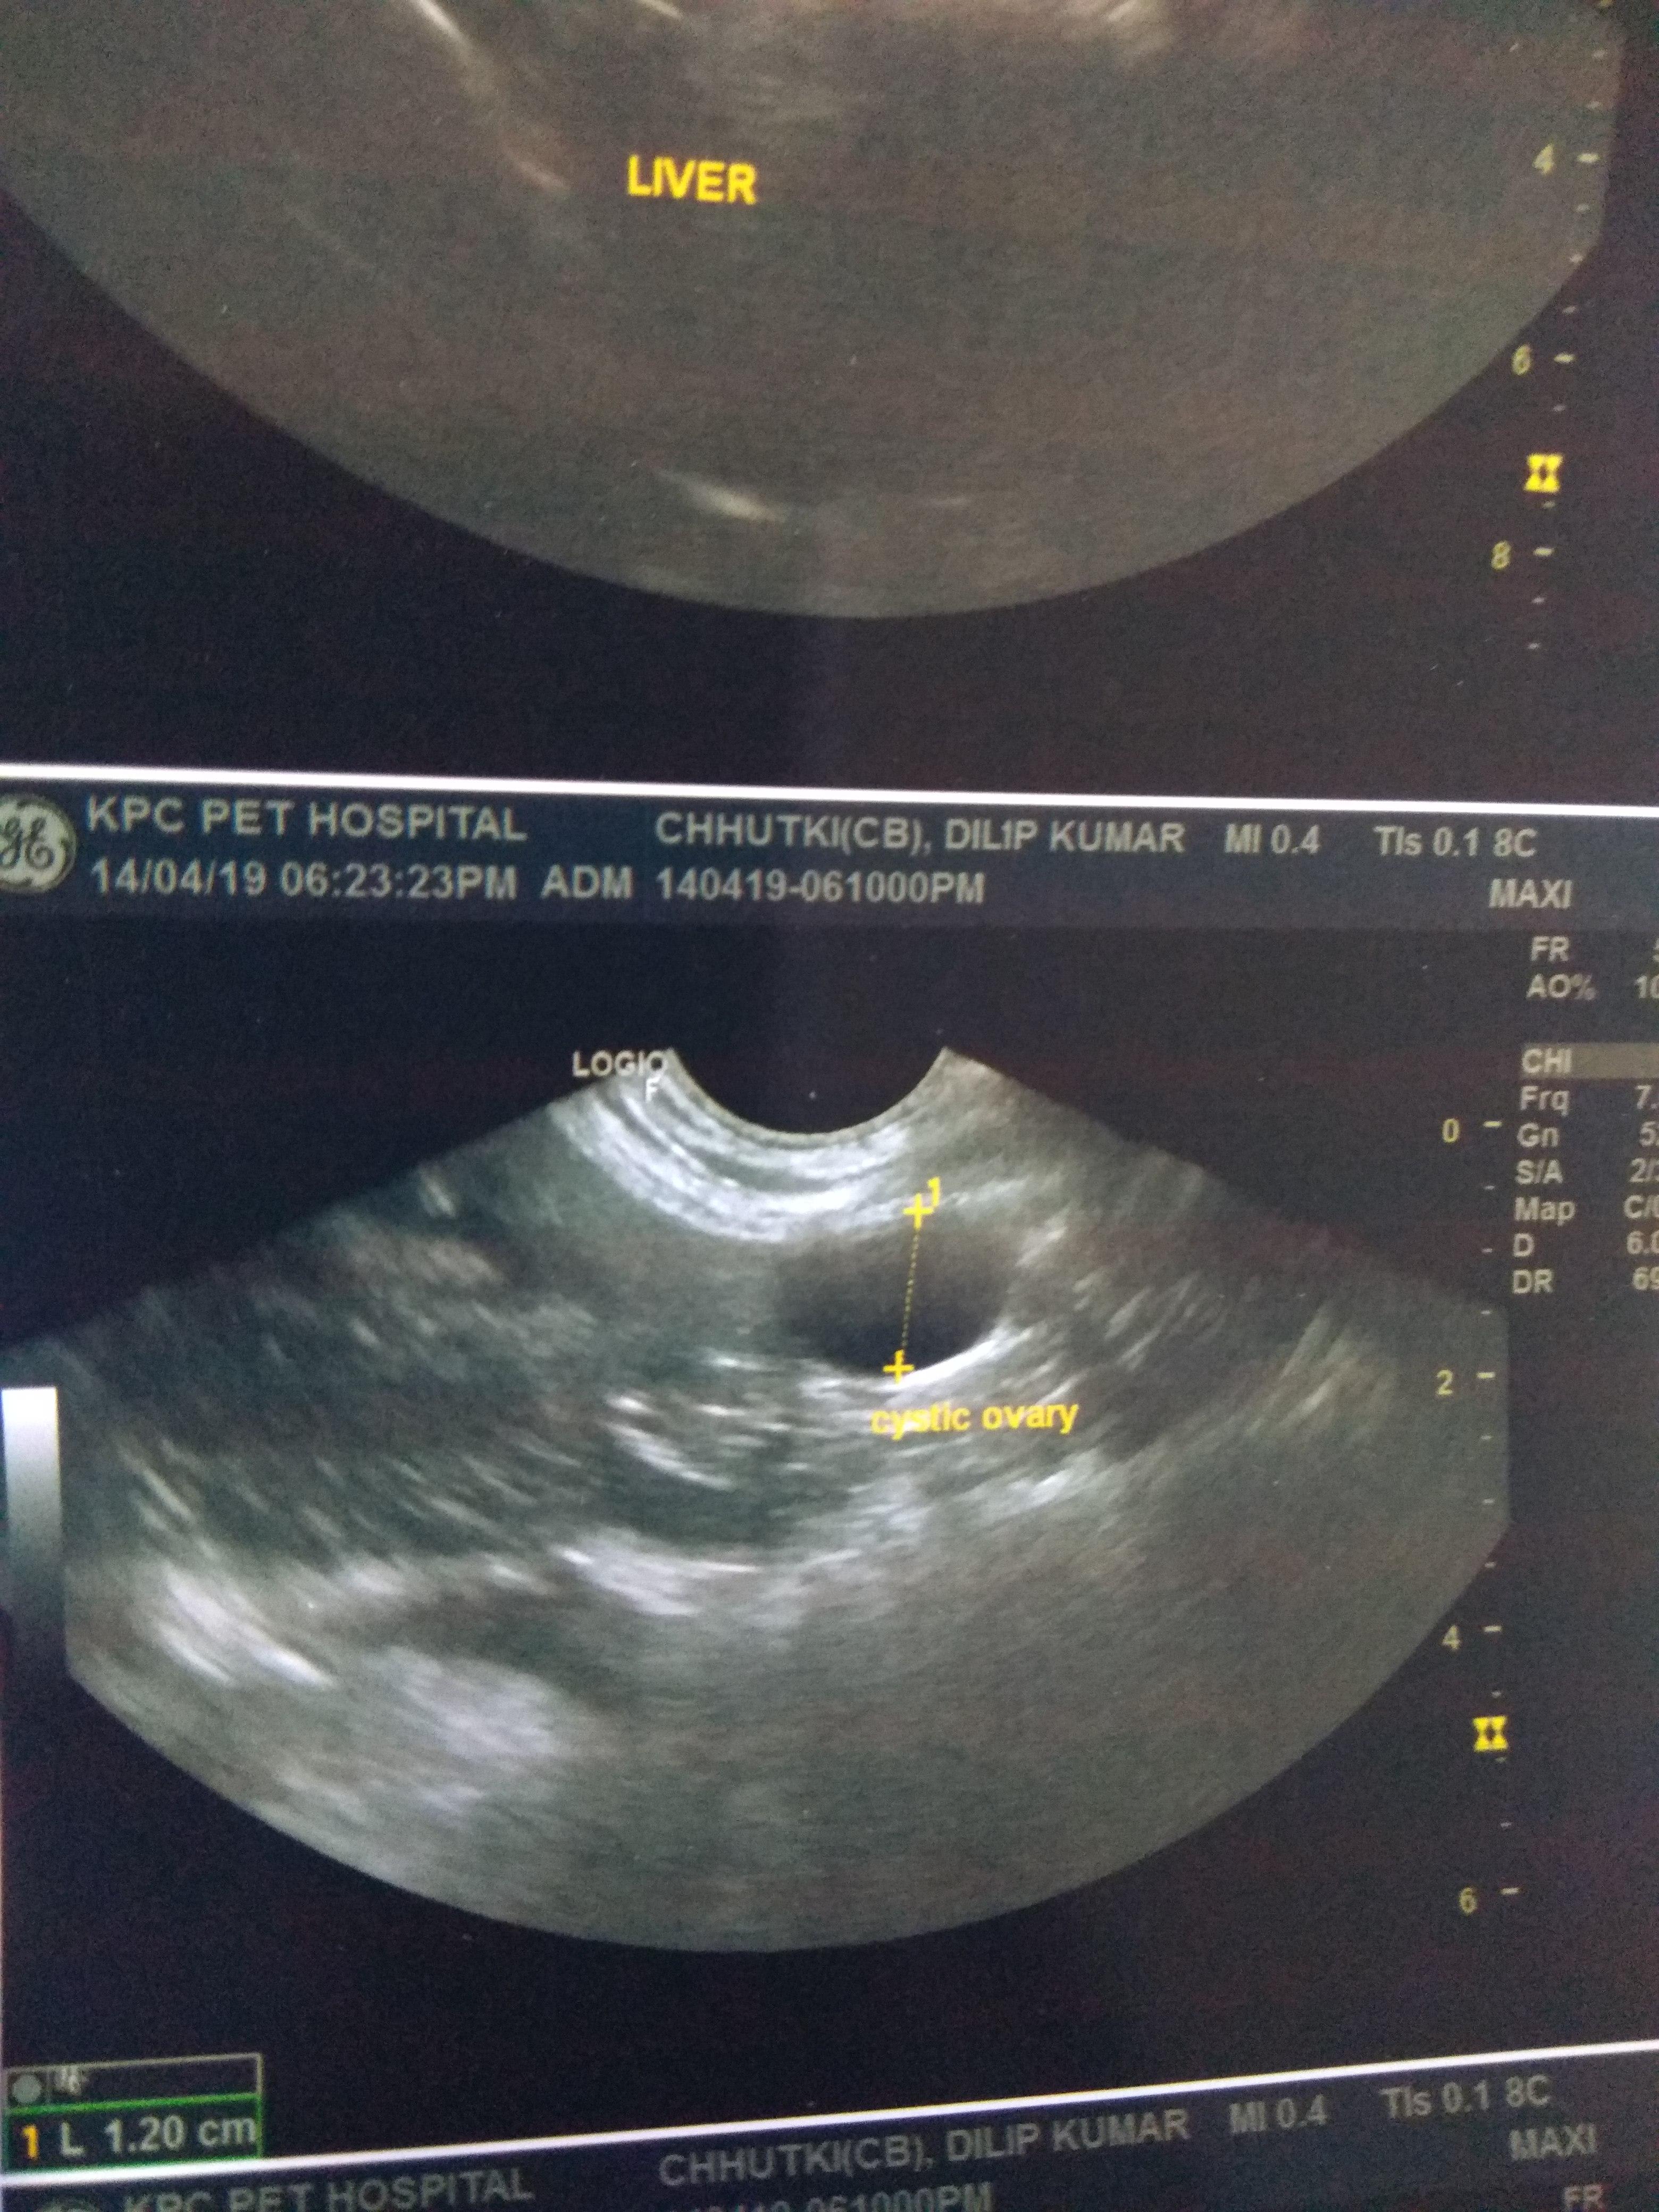

My dog is in heat n last month in USG cystic ovary in left side.she was never vaccinated for distemper.she is 8 yrs old n never dewormed also.she is not a puppy so does she need distemper vaccination?also is deworming needed before vaccination?I don't know if she has heartworms also if it is do then distemper vaccination b fatal?can distemper vaccination cause brain inflammation?vet told it will b a 7 in 1 shot so dangerous?heartworms (not sure)+ heat+cystic ovary+never dewormed+old age+shots?

This question includes photos that may contain sensitive content. Click to view.